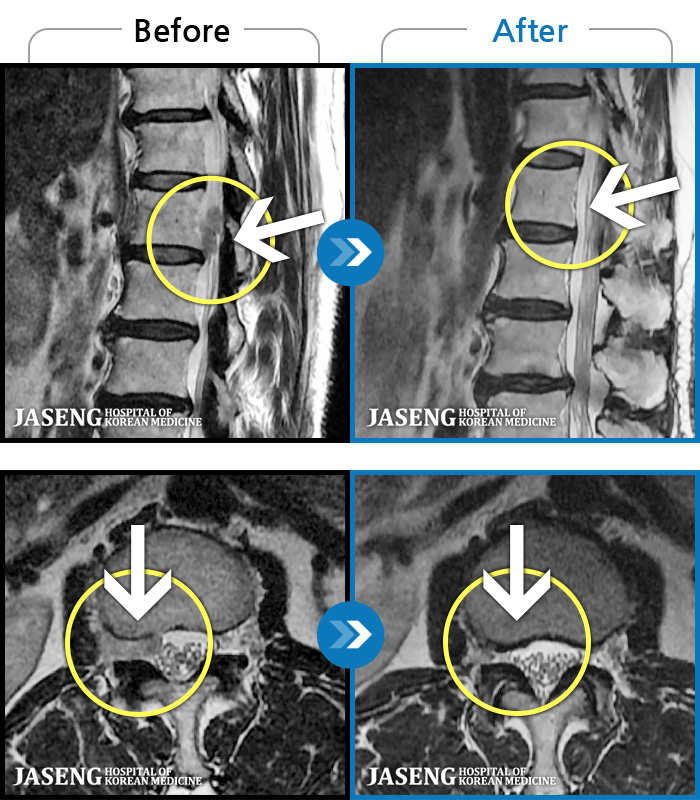

허리디스크

해운대 · 김상돈 원장

허리가 찌릿찌릿하고 찢어질 것 같은 통증

촬영시기

2024.01.08 ~ 2025.08.12

2025.08.29

조회수 271